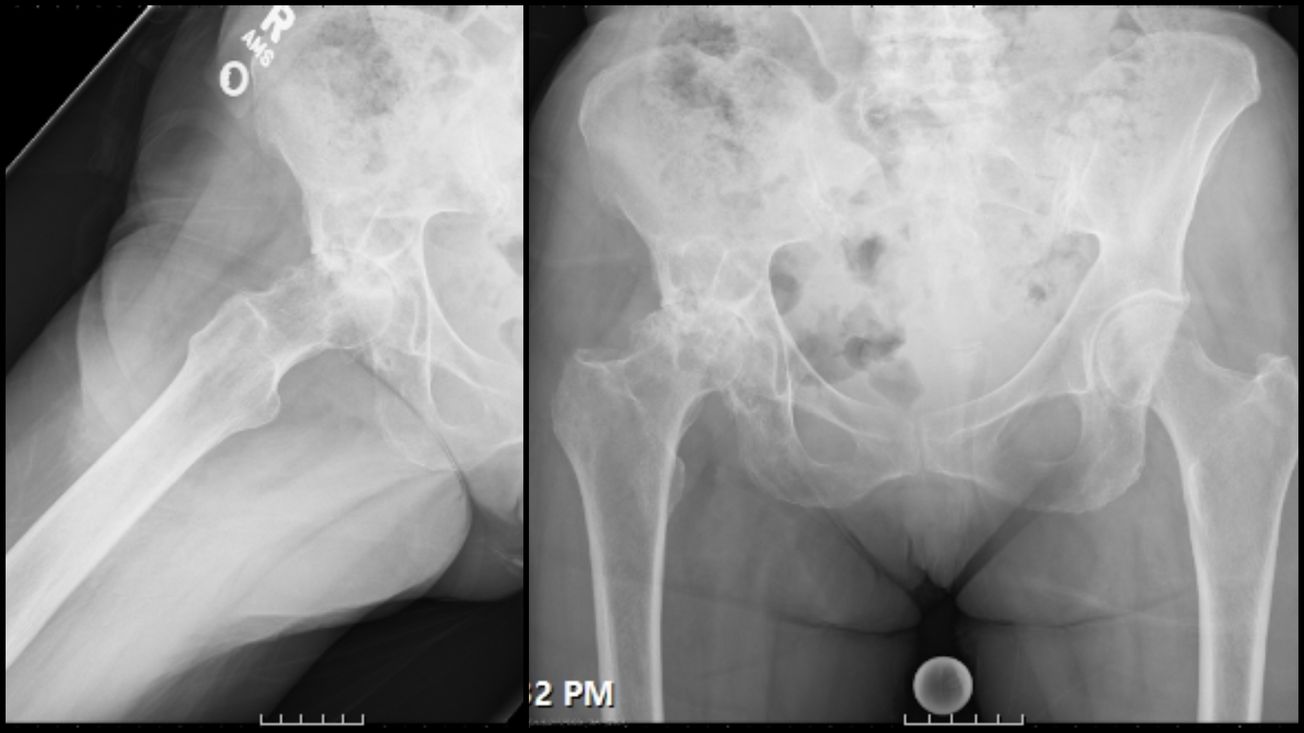

Total Hip Arthroplasty (Anterior)